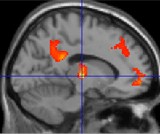

Diagram showing the tranquil brain

Study shows tranquil scenes have positive impact on brain. Tranquil living environments can positively affect the human brain function, according to researchers at the University of Sheffield. The research, which was published in the journal NeuroImage, uses functional brain imaging to assess how the environment impacts upon our brain functions. The findings demonstrated that tranquil environmental scenes containing natural features, such as the sea, cause distinct brain areas to become `connected´ with one another whilst man-made environments, such as motorways, disrupt the brain connections. The research involved academics from the University´s Academic Unit of Clinical Psychiatry, Academic Radiology and the School of Architecture, along with the School of Engineering, Design and Technology at the University of Bradford and the Institute of Medicine and Neuroscience at Jülich, Germany. The team carried out functional brain scanning at the University of Sheffield to examine brain activity when people were presented with images of tranquil beach scenes and non-tranquil motorway scenes. They utilised the fact that waves breaking on a beach and traffic moving on a motorway produce a similar sound, perceived as a constant roar, and presented the participants with images of tranquil beach scenes and non-tranquil motorway scenes while they listened to the same sound associated with both scenes.